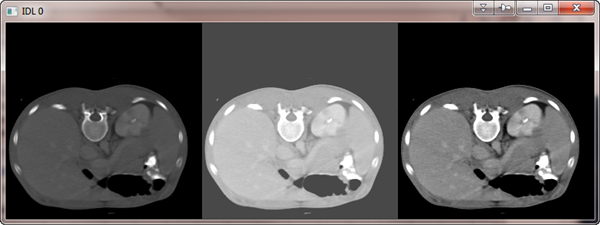

This is an image processing utility routine similar to BYTSCL, in that

it scales input data into the range of 0 to 255. But it uses the

standard deviation of pixels in the image to select upper and lower thresholds for the linear scaling. The standard deviation and mean

are calculated for the image (excluding any value specified with the

EXCLUDE keyword), then the standard deviation is multiplied by a

factor (specified with the MULTIPLIER keyword), before being

subtracted or added to the mean to select the lower and upper bounds

for a linear scaling.

Here is an example of how the program can be used.

image = cgDemoData(5)

cgDisplay, 256*3, 256

!P.Multi = [0,3,1]

cgImage, image

cgImage, cgSDevScl(image)

cgImage, cgSDevScl(image, Exclude=0)

!P.Multi = 0

Here is the output.